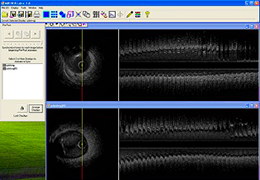

Multi-planar slicing.

Oblique slicing.

Side-by-side comparative assessment for pre- and post-operative scans.